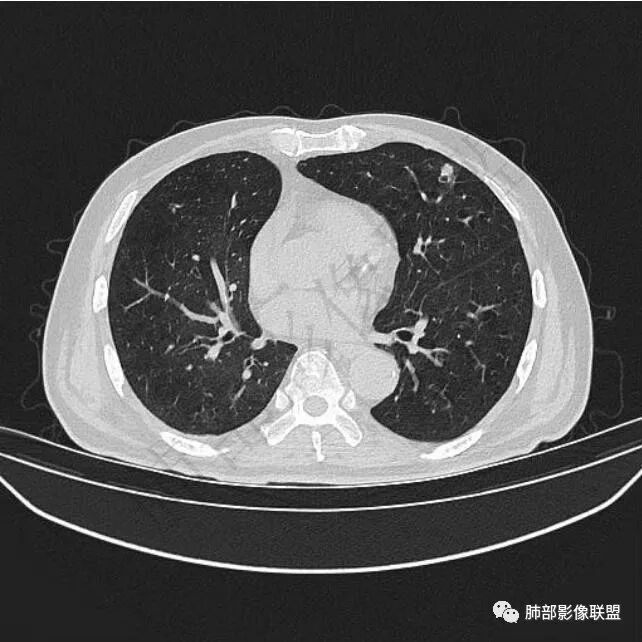

5年前鼻咽癌,2年前右肺上叶鳞癌手术史。

二..发现左肺上叶舌段实性密度小结节影,不规则略呈半环形,边界清楚,未见分叶、毛刺及磨玻璃晕。未见卫星病灶。

9个月后病灶明显增大,边缘较平直,部分膨隆,锁扣样外观,仍旧缺乏典型深分叶及张力,未见胸膜凹陷。

再1个多月后病灶继续增大,较明显不均匀强化,肺门一侧见低密度区。病灶边缘相对不清,可见毛刺。